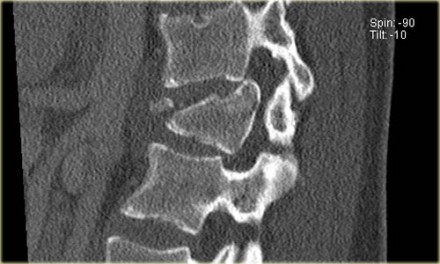

The findings are:

- Morphology: Burst - 2 points

There is retropulsion of a body fragment (black arrow) - PLC: widening of both facet joints (yellow arrow) and a fracture of spinous process (blue arrow) - 3 points

- TLICS based on imaging: 5 points

Discussion: based on only

these two images it is hard to say whether this is burst with

PLC-injury or maybe distraction on the posterior side.

In either case the TLICS-score is high and this patient is a surgical candidate.